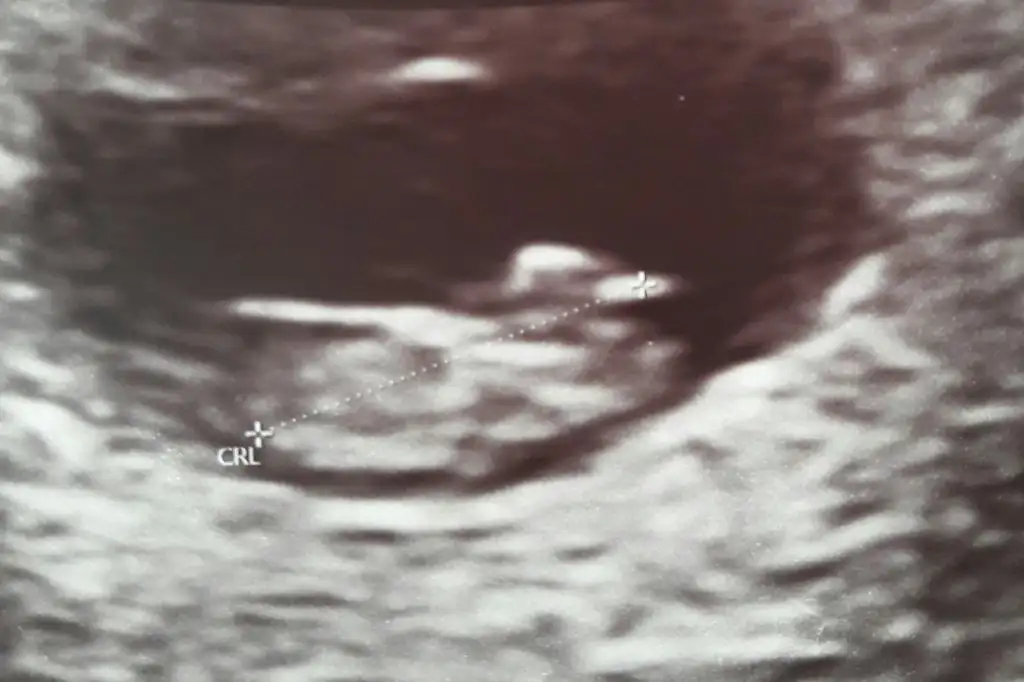

Kaç haftalık 11 12 13 hafta olmalı nublar kapalı kafa yapısı erkek gibi tutmayabilir nub için istediğim haftalarıda paylaşınBenimde bebeğime bakarmısınız dr ters olduğu için göremedi Eki Görüntüle 2619582 Eki Görüntüle 2619582 Eki Görüntüle 2619583

6-7 hafta olmalıBen hala cinsiyet öğrenemedim canım kontrole gidemedim yani plesentaya göre tahmini yeni duydum bakarmisin 10 haftalik burdaIkra meyra

Nub için 11 12 13 hafta olmalı sanki kız ama emin değilim istediğim usg leri paylaşınMerhaba bana da yorum yapabilir misiniz